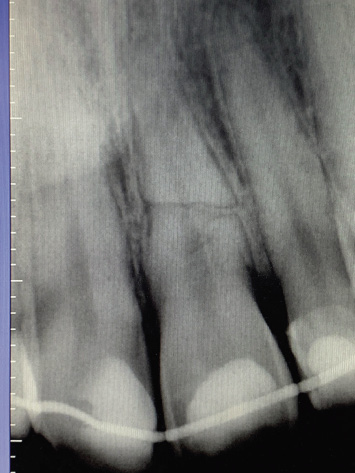

Se debe realizar Rx para confirmar, ubicar el nivel de la fractura y ver si existe desplazamiento coronal (Fig. 5).

Figura 5. Imagen radiográfica de fractura radicular.

Precisará de analgesia y cobertura antibiótica, y se deberá derivar de Urgencias a Odontología. En dentición temporal, hay que evitar el contacto oclusal y decidir si se realiza tratamiento conservador, en caso de que no exista desplazamiento de la corona o exodoncia, si existe desplazamiento o en edades muy próximas a la del recambio fisiológico de las piezas permanentes. Si se debe realizar la exodoncia, se puede realizar solo de la parte coronal y hacer un seguimiento evolutivo del fragmento radicular hasta que se produzca la reabsorción fisiológica del mismo. Se debe recomendar dieta blanda y si no se realiza la exodoncia, no utilizar el chupete.

En dentición permanente, el test de vitalidad puede dar resultados negativos por afectación pulpar transitoria o definitiva. En casos en que la corona fracturada del diente permanente se haya avulsionado, se debe intentar reimplantar, siguiendo el protocolo de los dientes avulsionados y ferulizar a los dientes adyacentes durante 4 semanas. En los demás casos de fractura radicular, también se debe realizar una ferulización a las piezas adyacentes. Cuanto más apical, es decir, cuanto más hacia al final de la raíz sea la fractura, menos probable es que pierda la vitalidad pulpar, y cuanto más coronal, peor pronóstico. También el aumento de la diástasis favorece la necrosis del fragmento coronal, incrementa su movilidad y empeora el pronóstico. Las fracturas horizontales tienen mejor pronóstico que las verticales.

Precisa de seguimiento evolutivo clínico y radiográfico del caso.